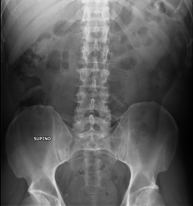

- Abdomen y pelvis

- RX Abdomen

Técnica mediante la cual, utilizando rayos X, se obtienen imágenes del abdomen (estómago, intestino delgado, intestino grueso, hígado, riñones, vejiga, pelvis ósea, etc.) para su estudio.

- RX Pelvis

Procedimiento mediante el cual, utilizando rayos X, se obtienen imágenes de la pelvis para su estudio, especialmente de los huesos pélvicos.